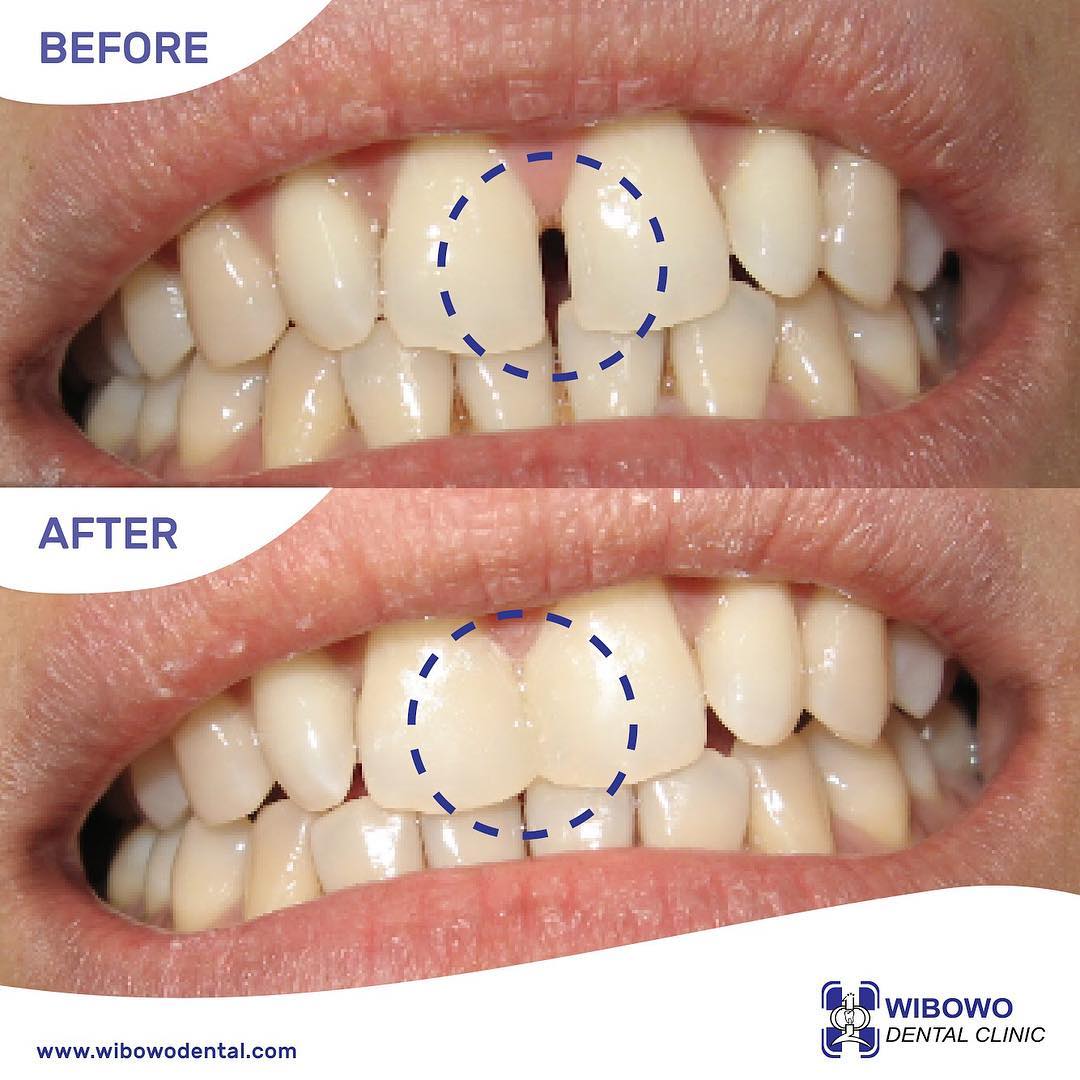

Eksis sejak tahun 1978, Wibowo Dental Clinic merupakan pionir Digital Dentistry di Surabaya. Mengedepankan perawatan yang terintegrasi dari tim dokter spesialis periodonsia, orthodonsia, dan konservasi gigi dan pengaplikasian teknologi terkini, Wibowo Dental Clinic telah dipercaya oleh berbagai kalangan, termasuk tokoh nasional.